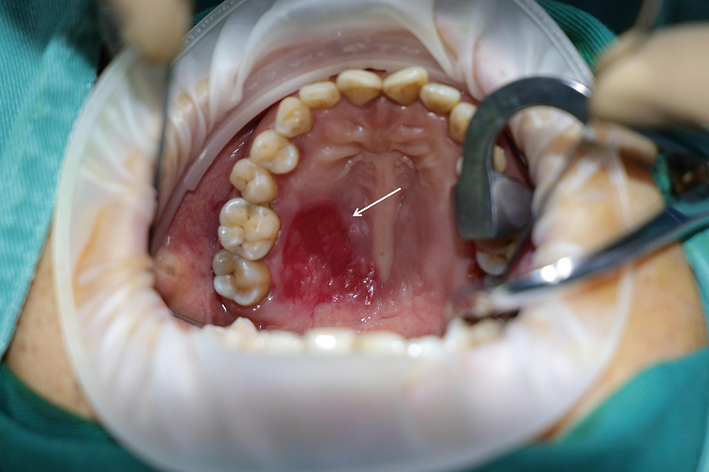

Mucoepidermoid carcinoma of the palate presenting as an erythematous lesion: A case report and literature review

Mucoepidermoid carcinoma (MEC) typically originates from major salivary glands but may also arise primarily from minor salivary glands in the palate. It can show diverse clinical symptoms, such as masses, pain, or ulcers. However, cases presenting primarily with mucosal erythema are relatively rare. This article reports a case of palatal MEC that presented erythema as the main clinical feature, and discusses its clinical characteristics, diagnosis, and treatment.